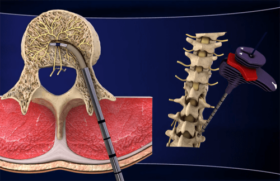

쉽게 진단이 되는 건강 문제들이 있다. 하지만 좌골 신경통처럼 다른 문제들과 증상을 착각할 수 있는 질병들도 있다. 계속 읽어가면서 좌골 신경통이 있는지…